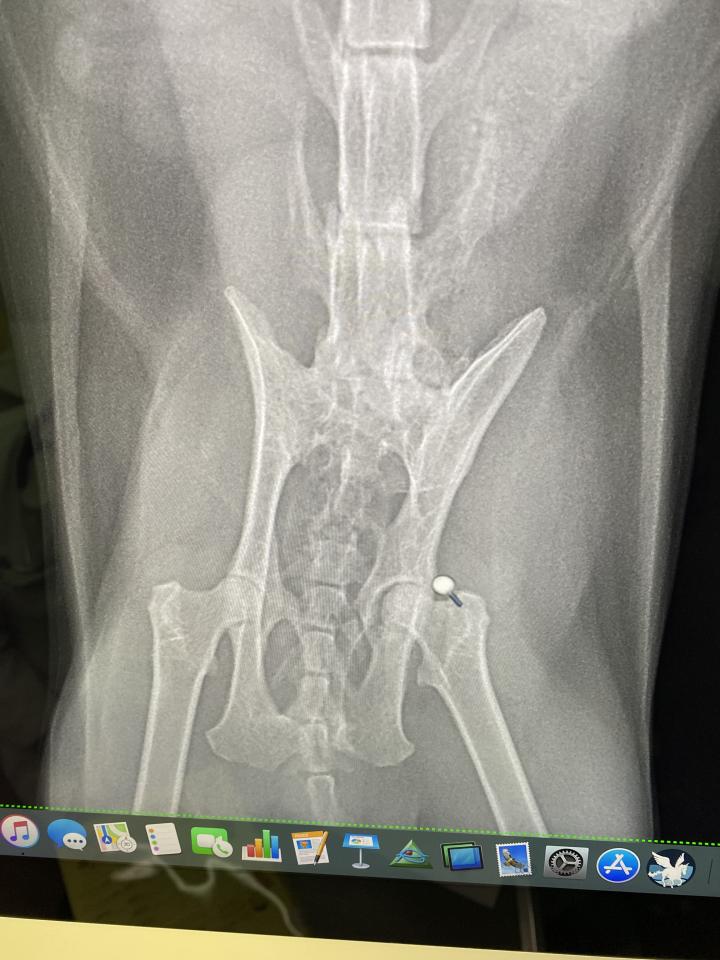

さらに手術の前に、全体の健康診断をしてもらった所、骨盤骨折歴があることが判明。

素人が見ても分かるくらい、骨盤が歪んでた。